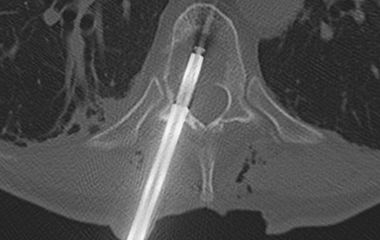

Aus diesem Grund besteht in unserer Fachabteilung ein eigener Schwerpunkt zur konservativen Behandlungsmöglichkeiten an der gesamten Wirbelsäule. Seitens der interventionellen Schmerztherapie bieten wir das gesamte Spektrum von Infiltration bis zur Thermokoagulation an.

Sollte eine Operation nötig sein, können wir mit großer Routine minimalinvasive Eingriffe inkl. endoskopischer Technik aber auch invasivere Stabilisierungen der Wirbelsäule (Spondylodese) an Hals- Brust- und Lendenwirbelsäule von vorne, seitlich oder hinten durchführen. Die Eingriffe werden wenn möglich minimalinvasiv und mit Hilfe einer Neuronavigation sicher durchgeführt. Kleinere Eingriffe können wir in Kooperation mit der Wertachklinik Bobingen auch dort durchführen.